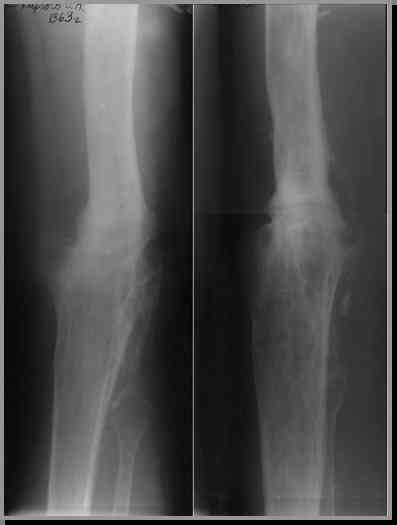

После нескольких некрэктомий, проведения аутодермопластики и заживдения ожоговой раны через 2 месяца после травмы произведен открытый остеосинтез левой бедренной кости штифтом и пластиной (деротационной) [image 01, 02]. Через 1 год и 7 месяцев после травмы у больного диагностированы ложный сустав и хронический остеомиелит левой бедренной кости. Произведено удаление металлических фиксаторов, секвестрэктомия и остеосинтез бедренной костивнешним двухплоскостным стержневым аппаратом [image 03, 04] .